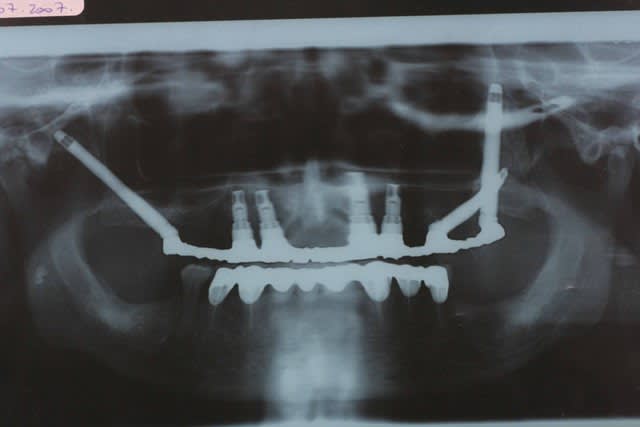

Un aperçu de mes preferes

Bouddha 2 wmj1zk - Eugenol

10/12/2007 à 22h24

Je retente la photo